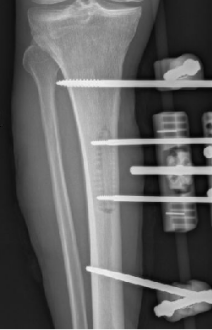

多年来,贵州航天医院各科室紧跟医学前沿,不断强技术、补短板,大力开展新技术、新项目,完成了许多高精尖、高难度、本地区“首例”的技术,填补了医院医疗技术空白,满足了群众日益增长的医疗需求。 贵州航天医院骨科率先在遵义地区开展骨搬移技术,截至目前,已治愈慢性骨髓炎、感染性骨不连、骨缺损、脉管炎、糖尿病足患者200余例,糖尿病足治疗保肢率达到98%。 本期,我们将为大家带来骨科特色技术——骨搬移技术(Ilizarov)。 案例分享 一名59岁的患者,身患糖尿病12年,在来我院3个月前出现了右脚溃烂的症状,来院就诊时,患者的右脚十分红肿,右脚脚趾坏死,伤口处不断流出黑红色脓液,情况十分严重。在接诊到患者时,骨科专家团队高度重视,立刻为患者完善了CT血管造影(CTA)等相关检查,诊断为:2型糖尿病,糖尿病周围血管病变,右糖尿病足。 术 前 考虑到患者情况比较严重,为最大限度保证患者肢体完整,科室专家团队进行了严格的讨论评估,为患者制定了骨搬移技术治疗方案,在征得患者及其家属的同意后,成功通过搬移骨块为患者进行治疗,促进患者病变肢体血管再生。 胫骨横向骨搬移外架固定 清除感染病灶 术后调节外架,通过搬移骨块 促进患肢血管再生 患者在术后三周前来换药,观察到感染得到进一步控制;术后六周复查,患者病变处已愈合,进行CT血管造影(CTA)后可明显观察到足部血管再生。 术后3周 术后6周愈合 CT血管造影见足部血管再生 糖尿病患者全身与局部的问题互为影响,形成恶性循环,糖尿病足溃疡创面迁延不愈,常见干性坏疽、湿性坏疽、趾坏死、深且大的溃疡以及骨髓炎等症状,还可导致脓毒血症,以往为保全生命,患者被迫选择一次或多次截肢。骨搬移技术的发展进步,能在血糖有效控制、局部有效清创下,有效促进患肢微血管再生,改善患肢血供,达到糖尿病足更快治疗康复的目的,并能根据病变情况最大限度的保障患者肢体完整。 什么是骨搬移技术 骨搬移技术是通过使用专用的骨外固定器固定骨段,每天缓慢牵拉,在牵拉搬移过程中,骨段尾部形成新骨及新的软组织,从而修复骨骼缺损及软组织缺损。是治疗大段骨缺损、骨不连、骨感染、肢体畸形的金标准方法,也用于治疗脉管炎、糖尿病足等肢体缺血性疾病。 骨感染缺损 切除感染段 搬移骨段 新骨形成 骨感染根治愈合 骨搬移技术原理 生物组织在持续、稳定、缓慢牵拉下,能刺激细胞分裂、组织再生,骨外固定技术运用该原理,通过持续缓慢调节外固定器形成牵拉张力,促进牵引成骨与相邻组织再生,如神经、血管、肌肉、皮肤等再生,达到治疗大段骨缺损、肢体缺血如糖尿病足等疾病的目的。 骨搬移技术优势 (一)除治疗骨缺损、骨不连外,有更广的适用范围,利用组织再生、血管再生等特性,能大量运用于肢体畸形的矫形、糖尿病足等的治疗。 (二)治疗效果确切,重建肢体外型和功能,极大降低截肢率和残疾率。 (三)明显提高了患者生活质量,极大减轻其家庭及社会负担。 肢体畸形的矫形 慢性骨髓炎 骨段切除 术后1年 濒临截肢的脉管炎术后6周 难愈创面术后3周 贵州航天医院骨科 专家团队 赵学平 骨科主任 主任医师 临床擅长:从事骨科临床工作30余年,对骨科常见疾病的诊治具有丰富的临床经验。 世界中医药联合会脊柱康复专业委员会常务理事,中华中医药学会整脊分会常务委员,中国中西医结合学会骨伤科分会肢体矫形功能重建与康复专家委员会常务委员,中国研究性医院学会骨科创新与转换专业委员会关节外科学组保髋工作委员会常委,中国康复技术转化及发展促进会骨外科与康复技术转化专业委员会常务委员,泛珠三角区域运动医学联盟(PPRD-SMA)理事会常务理事,中国研究型医院学会运动医学专业委员会委员,贵州省中医药学会整脊分会副主任委员,贵州省中西医结合学会银质针专业委员会副主任委员,贵州省康复医学会骨与关节专业委员会常务委员,贵州省人民医院骨科专科联盟常务理事,贵州省康复医学会骨内科专业委员会常务委员,中华医学会贵州省骨科学会委员,贵州省康复医学会脊柱脊髓专业委员会常务委员,贵州省运动医学分会委员,贵州省康复医学会骨与软组织肿瘤专业委员会委员,遵义市医学会创伤分会副主任委员,贵州省康复医学会骨内科专业委员会遵义地区分会常务委员,遵义市医疗事故鉴定、伤残鉴定、工伤鉴定、司法鉴定专家。 长期从事骨科临床研究及教学工作,在国家级、省部级杂志发表论文20余篇,SCI论文2篇,参与主编骨科专著2部,主持省部级科研项目2项,参与指导省部级、市级科研项目6项。 陈明勇 骨科副主任 副主任医师 临床擅长:从事创伤骨科工作约20年,对骨缺损、骨不连、骨肿瘤、肢体畸形等的肢体矫形重建及功能重建,慢性化脓性骨髓炎的根治治疗、糖尿病足的保肢治疗、快速康复理念(ERAS)下的老年骨折的诊治,四肢复杂骨折的诊治,四肢骨折等微创手术治疗具有丰富的临床经验。 2004年毕业于遵义医学院临床专业,曾在中国人民解放军总医院、广西医科大学第一附属医院、上海第六人民医院骨科进修。中国中西医结合学会骨伤科专业委员会横向骨搬移治疗糖尿病足及微血管网再生学组首届委员,遵义市医学会创伤分会常务委员。 瞿 辉 骨科 副主任医师 临床擅长:对骨科的常见病、关节外科、脊柱外科及运动医学疾病的诊治具有丰富的临床经验,熟练掌握骨科手术操作技术。 毕业于遵义医学院临床医学系,2005年前往广州中山大学第一附院骨显微医学部进修学习,2011年前往成都华西医院进修学习,并多次在省内外学习骨科相关知识,是中华医学会骨科分会会员。 赵兴东 骨科 主任医师 临床擅长:擅长骨科的常见病及各种创伤、四肢骨折创伤修复、骨感染、手足疾病的诊治和手足体表畸形的矫形整复,熟练掌握骨科四肢骨病及创伤的手术操作技术,尤其在四肢关节复杂性损伤、手足外伤、组织缺损创面、难治创面的皮瓣修复方面及平足、高弓足矫形方面及四肢慢性疼痛诊治、康复方面具有丰富的临床经验。 硕士研究生,毕业于遵义医学院临床外科系,2015年前往山东省立医院手足外科进修学习;遵义市医学分会创伤分会第一、二届委员,遵义市手外科医学会第二委届员会常务委员;在省级及省级以上期刊发表文章9篇,参编著作2部,参与主持并完成市级课题1项,参与市级课题2项、省级课题1项。 张俊凯 骨科 副主任医师 临床擅长:从事骨科临床工作28年,对创伤骨折、骨感染、骨缺损、骨不连等外科诊治,四肢骨折的微创手术治疗,四肢复杂骨折(如关节内粉碎性骨折、多发骨折等)的损伤控制及手术治疗等具有丰富的临床经验。 1995年毕业于遵义医学院临床专业,2009年前往复旦大学附属医院骨科进修1年。 卢懿明 骨科 副主任医师 临床擅长:从事骨科工作18年,对创伤骨折、四肢骨折的微创手术治疗、四肢复杂骨折(如关节内粉碎性骨折、多发骨折等)的损伤控制及手术治疗,尤其是髋部骨折的PFNA等微创技术,踝关节骨折、膝关节周围骨折的Mipo微创技术等具有丰富的临床经验,开展了4项新技术,发明6项新型专利技术。 2005年毕业于遵义医学院临床专业,2017年,前往南方医科大学第三附属医院骨科进修半年,回院后运用Mipo技术对骨干骨折及干骺端骨折的治疗技术,同时积极开展骨盆骨折、髋臼骨折腹直肌外侧切口的应用;发表了多篇专业论文,经常参与省内外学术交流会授课,获得医院荣誉称号多个。 邬夏荣 骨科 副主任医师 临床擅长:从事骨科工作16年,对四肢复杂骨折、骨肿瘤的诊治,尤其是足踝创伤、慢性踝关节损伤、平足症等诊疗具有丰富的临床经验。 2006年毕业于遵义医科大学临床医学专业,曾在陆军军医大学西南医院进修学习,发表多篇骨科学术论文。 余德怀 骨科 副主任医师 临床擅长:从事骨科工作10余年,对运动医学、骨关节、脊柱外科常见病、多发病的诊治具有丰富的临床经验。 硕士研究生,2011年毕业于遵义医学院临床医学专业,曾前往遵义医科大学附属医院运动医学专业进修学习;是贵州省医学会运动医学分会青年委员,西部关节镜联盟委员;发表多篇骨科学术论文。 冯 乾 骨科 副主任医师 临床擅长:从事骨科工作近20年,熟练掌握骨科多发病及常见病的诊治,尤其对脊柱退变性疾病的诊断及治疗具有丰富的临床经验,主要研究脊柱微创相关治疗方式,能熟练开展椎间孔镜及VBE。 曾前往北京大学第三医院进修学习疼痛及椎间孔镜、首都医科大学友谊医院专业进修脊柱内镜;是贵州省康复医学会第三届脊柱脊髓专业委员会委员;发明专利3项、发表脊柱外科专业论文多篇。 张艳金 骨科 副主任医师 临床擅长:从事骨外科工作16年,对复合伤、多发伤的救治、四肢骨干骨折、关节周围骨折、骨肿瘤、骨髓炎等诊治具有丰富的临床经验。 中共党员,硕士研究生,2006年本科毕业于山西医科大学第二临床医学院,2011年研究生毕业于北京军区总医院;在“老年COPD患者合并髋部骨折的诊治”国际合作课题组研究两年,在老年髋部骨折的诊治方面具有丰富的经验,并发表论文6篇;承担遵义市级课题1项;承担遵义医科大学的临床教学工作,获得遵义医科大学优秀带教老师荣誉。编撰有《骨科疾病诊疗精粹》一书,开展2项新技术,编撰地方规范《务川自治县创伤骨科常见疾病诊疗规范》一书。 赵小锋 骨科 副主任医师 临床擅长:从事骨科临床工作11年,对骨科常见病、多发病诊疗有较为丰富的临床经验,擅长脊柱相关疾病诊断及治疗,尤其是颈、腰、腿疼痛疾病诊断及治疗,擅长胸腰椎骨折微创经皮穿刺内固定术、经皮穿刺椎体成形术、经皮穿刺脊柱内镜下腰椎间盘摘除术、单纯开创腰椎间盘摘除术、腰椎滑脱复位椎间植骨椎融合内固定术、腰椎管狭窄减压融合内固定术及人工髋、膝关节置换术等。 2012年毕业于遵义医学院外科学专业硕士研究生,2019年参加“遵义市115医学人才精英计划”于上海交通大学第一附属医院培训学习,2023年于北京大学第三人民医院脊柱外科进修学习,曾获得遵义市优秀医师荣誉称号。 遵义市手外科第一届委员,遵义市医学会创伤分会第一届委员,遵义市医学会创伤分会第二届委员,贵州省康复医学会第三届脊柱脊髓专业会委员,遵义市医学会烧伤与整形外科学分会委员,发表论文5篇,其中国家级核心期刊1篇,SCI论文1篇,主持市级课题1项并结题,参与市级课题2项。 贵州航天医院骨科简介 基本情况 贵州航天医院(原3417医院)骨科组建于1968年,前身是以创伤和断肢(断指)再植闻名于世的上海市第六人民医院骨科,中国断肢(断指)再植的奠基者、中科院院士陈仲伟等著名专家、学者多次莅临科室指导医疗、教,是贵州省最早拥有专业骨科技术科室之一,在70年代开展了贵州省首例断肢(断指)再植手术。组建50余年来,诊治患者已逾百万,挽救了无数的伤病员,成为了保障遵义地区人民群众健康的重要支撑。 经过几代人的不懈努力,今天的骨科,已由创伤骨科发展至骨病、骨肿瘤、骨结核等领域,现有脊柱外科、关节外科、四肢创伤、手足外科四个亚专科,成为了集医疗、教学、科研于一体的综合学科,是贵州省临床重点专科、遵义市临床重点专科、遵义市骨科临床医学中心、遵义市基层骨科专科联盟理事长单位。 科室目前开放床位110张,共有医护人员50余人,副高级以上专家18人,硕士研究生15人。拥有一流骨科医疗设备多台,每年不定期选派优秀技术骨干到全国各大知名医学院校进修、学习、参观、交流,并邀请国内、国外知名专家教授来院进行交流、指导,通过不断引进国内外先进的诊疗技术,科室医疗技术水平稳步提升,为广大人民群众提供了优质的医疗服务。 专科特色 骨一科 (一)骨缺损、骨不连的肢体与功能重建 胫骨横向骨搬移技术治疗糖尿病足: (二)慢性骨髓炎的根治治疗 (三)肢体缺血性疾病如糖尿病足、脉管炎的保肢治疗 (四)皮瓣修复 (五)复杂创伤的治疗 (六)老年髋部骨折及小儿骨折快速手术 老年髋部骨折: 骨二科 (一)胸腰椎骨折微创经皮椎弓根螺钉固定术 (二)老年性骨质疏松性患者腰椎滑脱脊柱内固定术(骨水泥螺钉) (三)V形双通道脊柱内镜技术(VBE)腰椎融合术治疗腰椎退行性疾病 (四)老年性骨质疏松性骨折(PVP/PKP)术 (五)人工髋关节置换术 (六)双侧股骨头坏死人工全髋关节置换 (七)右侧全髋置换术后假体周围骨折翻修 (八)人工膝关节置换术 (九)人工膝关节假体松动翻修 (十)关节镜技术 传统手术切口 关节镜技术切口 诊疗范围 骨一科 1.四肢创伤、矫形。 2.手、足踝外科。 骨二科